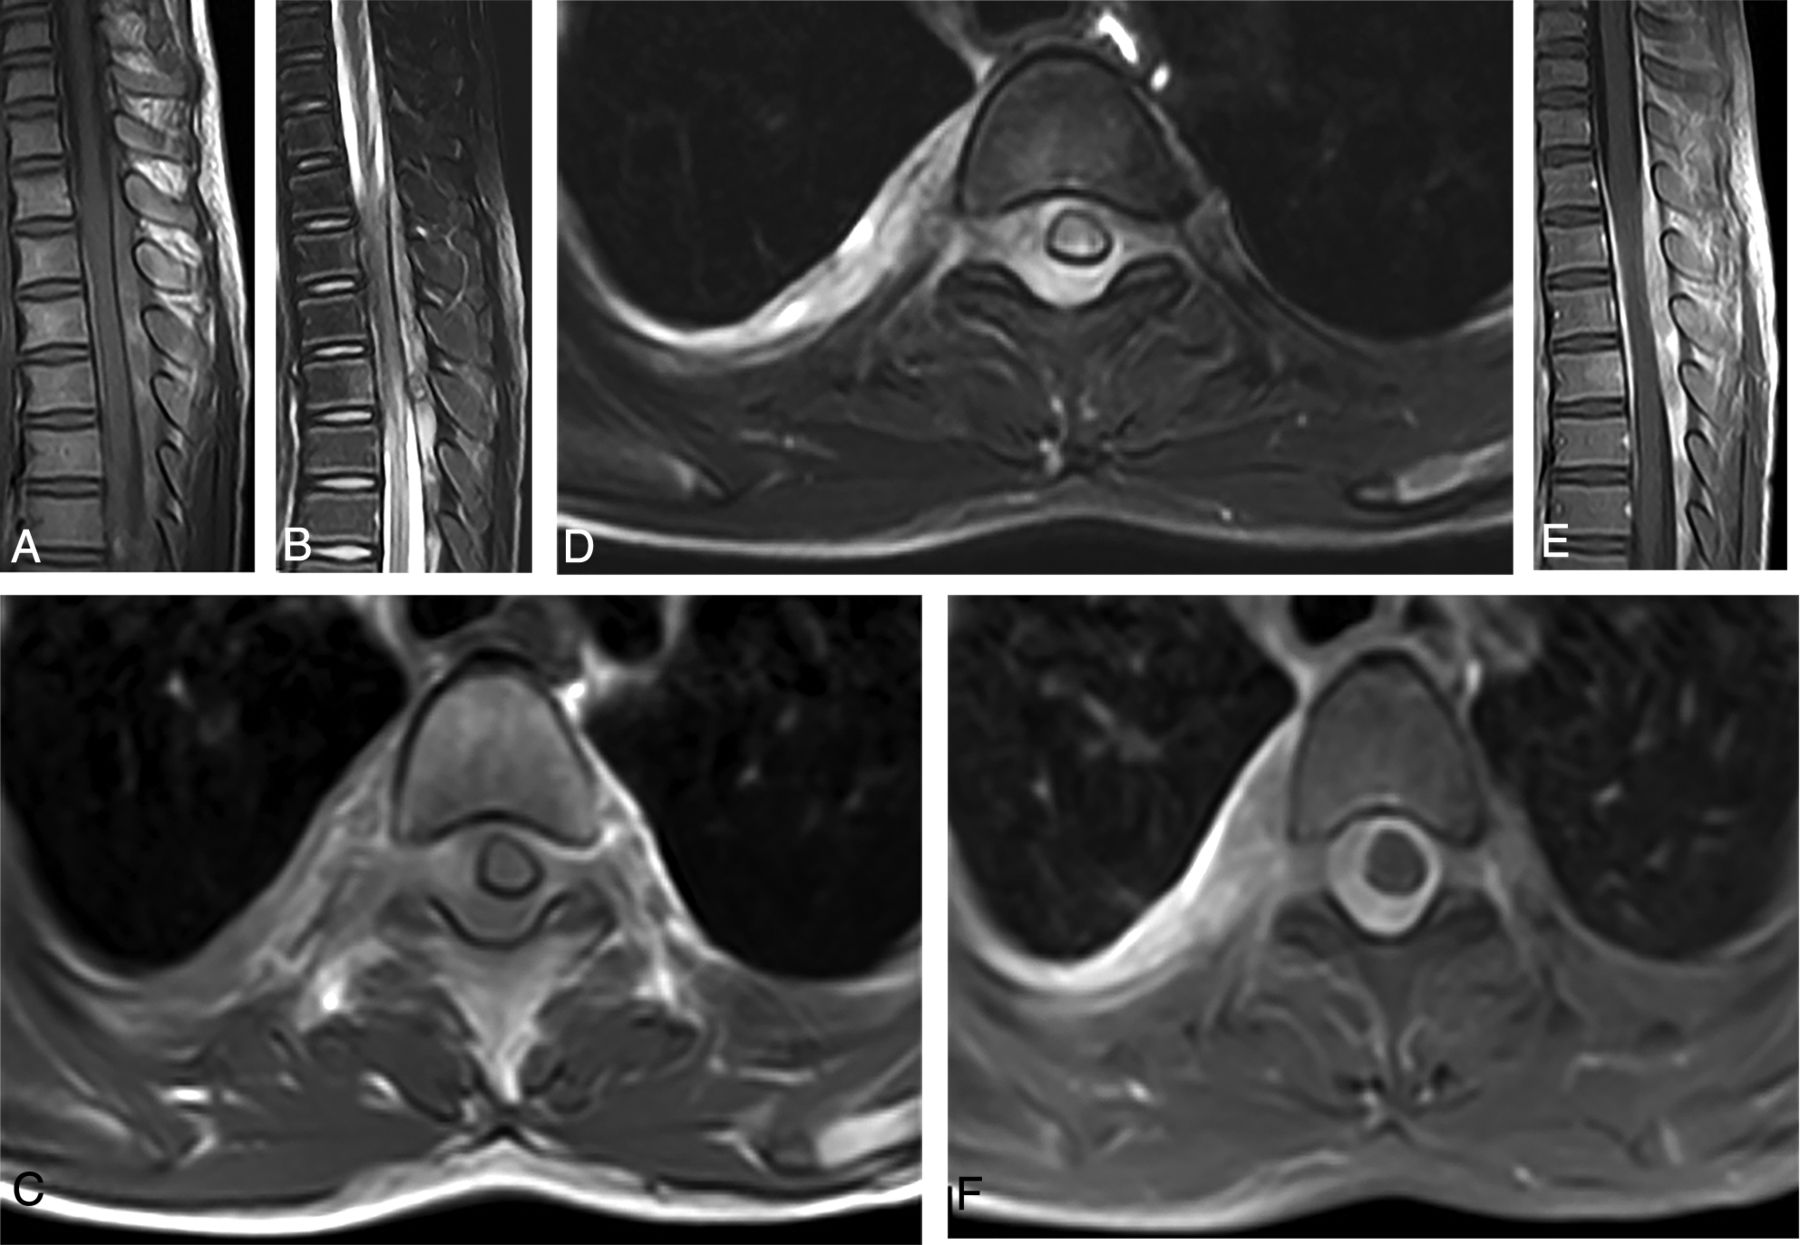

Five lesions were located within the thoracic spine (Figs 1A, -B), while 1 lesion was located in the junction of thoracolumbar segments (Figs 2A, -B). In the axial direction of the spine, all 6 lesions involved the intraspinal extradural space; additionally, the 6 lesions were all connected with the pleural lesions through the intervertebral foramen (Figs 1C, -D and 2C, -D).

The sagittal view showed fusiform-shaped (5/6) or bean-shaped (1/6) masses in the extradural space, and the longitudinal diameter passed 4–10 vertebral bodies, with a length ranging from 5.9 to 16.7 cm. The axial view showed that the granulomatous lesions of the 6 patients were all connected to pleural lesions (including pleural thickening in 6, pleural effusion in 4, and subpleural nodules in 4) through the intervertebral foramen, similar to the dumbbell-like sign (Figs 1C, -D and 2C, -D).

The plain MR imaging scan of the 6 granulomatous lesions showed mixed signals with predominant isointensity on T1WI (Figs 1A, -C and 2A, -C) and hyperintensity on T2WI (Figs 1B, -D and 2B, -D), of which 5 fusiform-shaped lesions presented with multiple patchlike or irregular hemorrhagic foci with hyperintensity on T1WI within the masses (Figs 1A, -C and 2A, -C). The 5 patients undergoing the enhanced MR image showed heterogeneous and marked enhancement in the granulomatous masses (Figs 1E, -F and 2E, -F). The lesions in the intervertebral foramen and the pleura showed an enhancement pattern that was similar to that in the intraspinal lesions (Figs 1F and 2F). Furthermore, there was enhancement in the adjacent spinal meninges (Figs 1E and 2E).